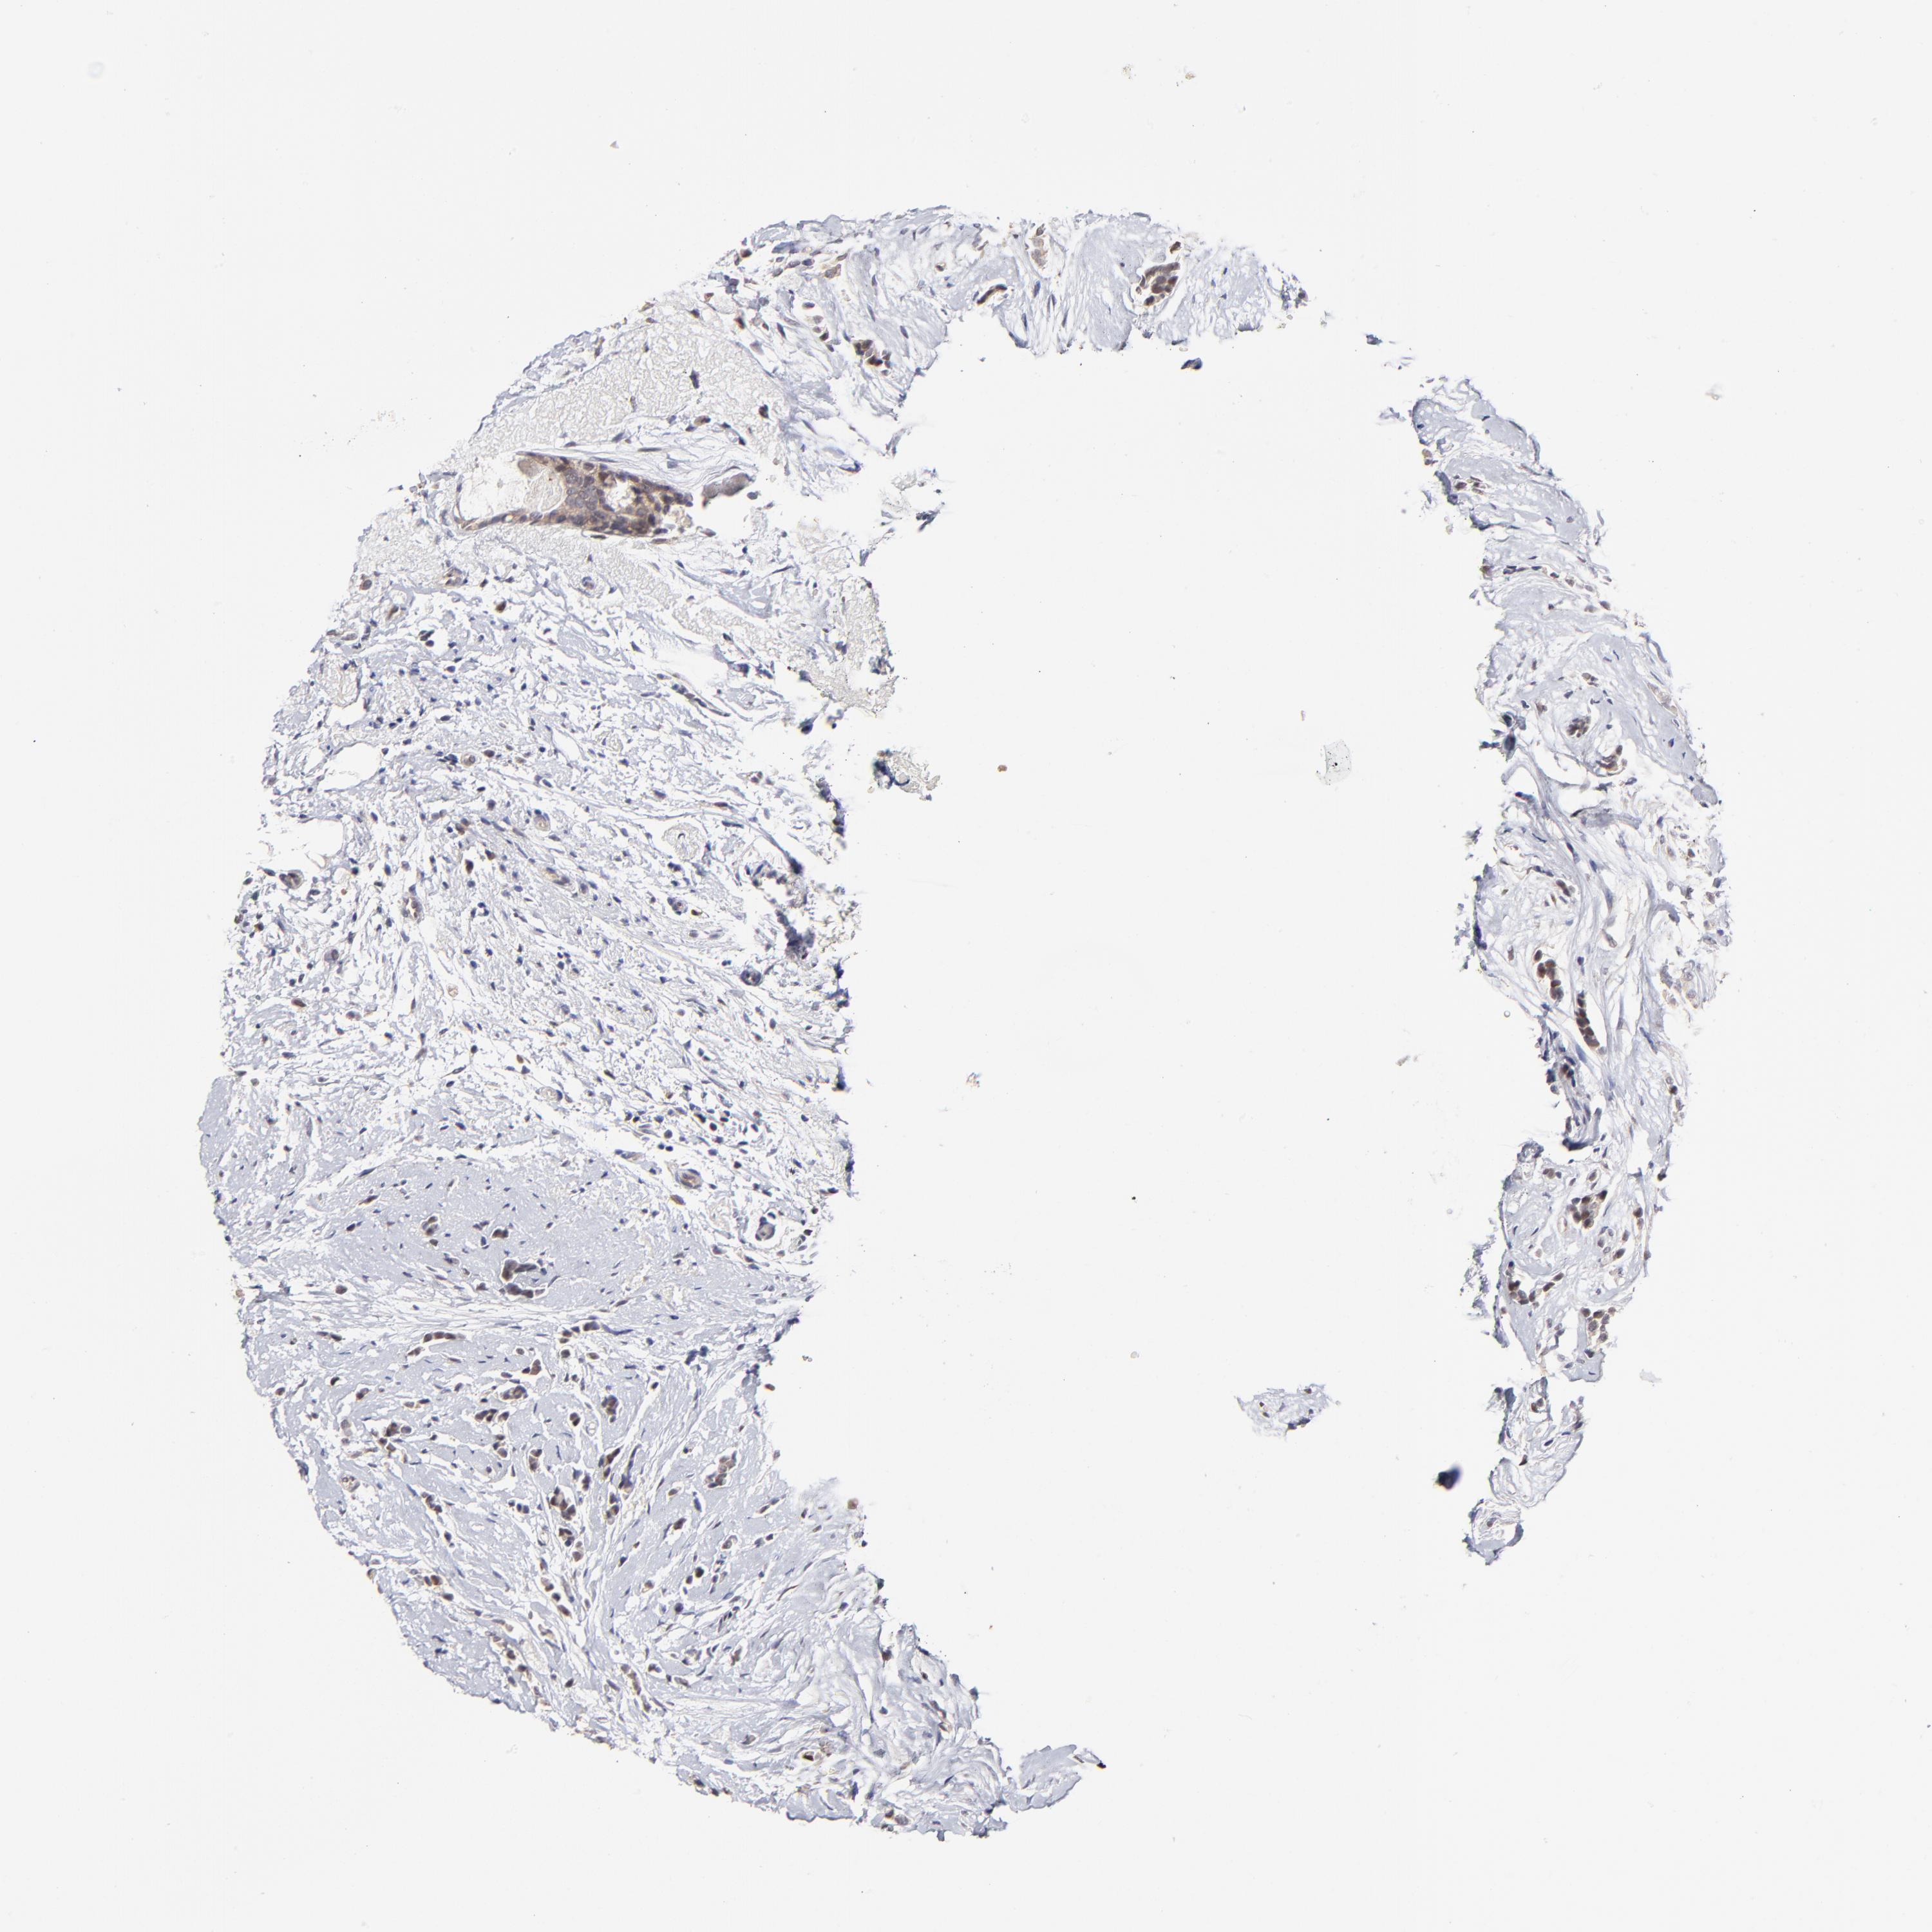

ZNF10

CANCER BREAST CANCER Show tissue menu

BRCA TCGA BRCA VALIDATION PROTEIN EXPRESSION

ZNF10 is not prognostic in Breast Invasive Carcinoma (TCGA)